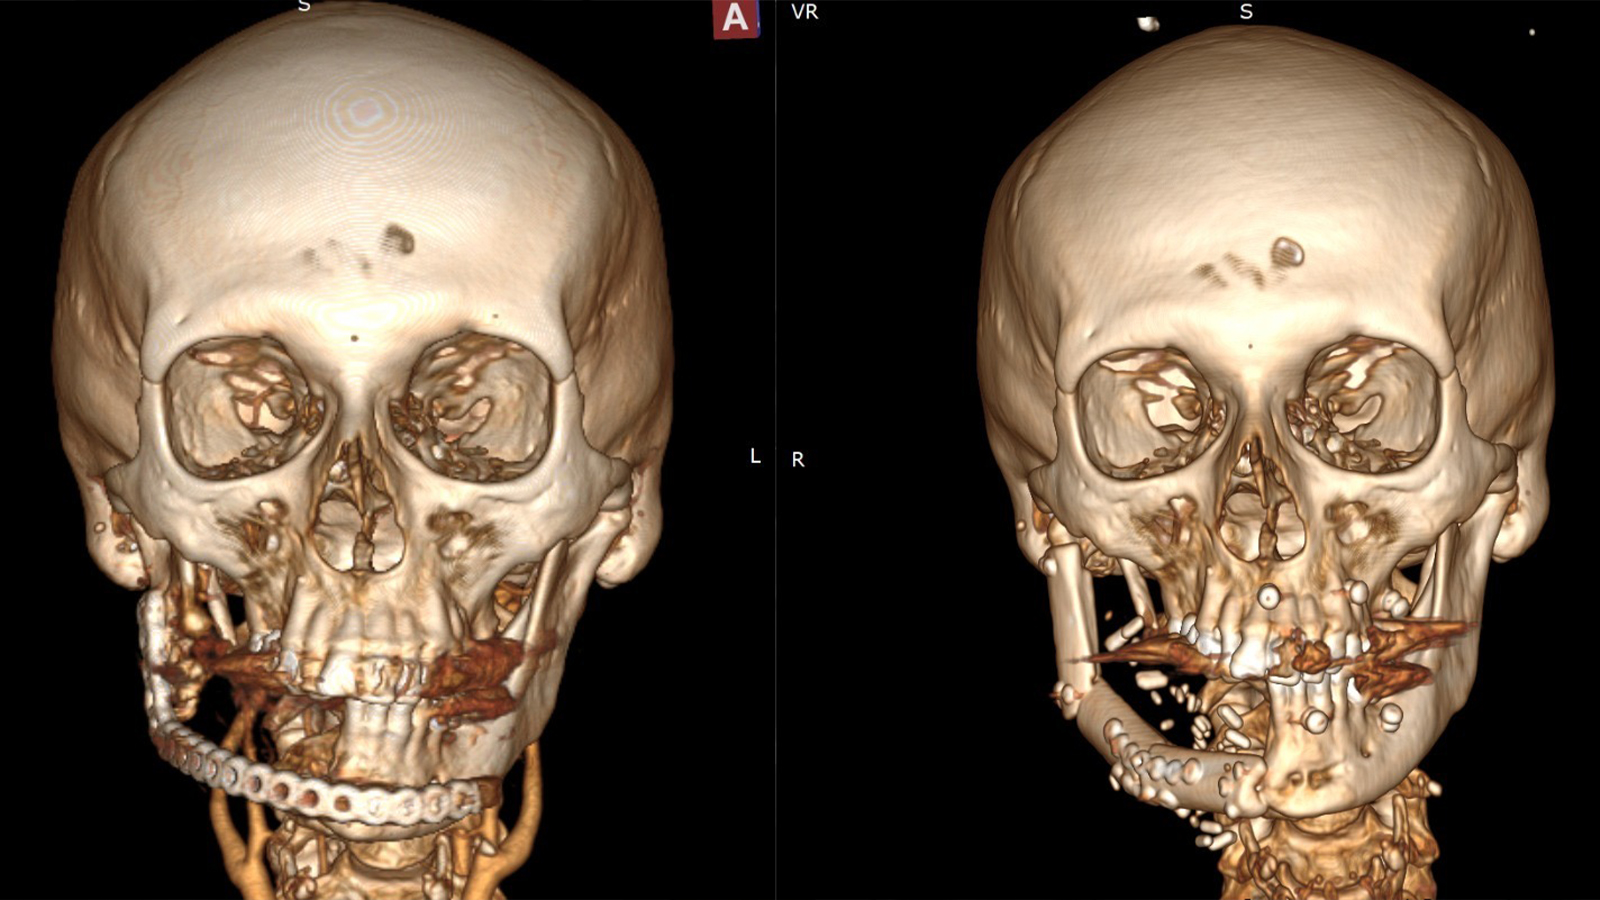

Bir il yarım əvvəl pasiyentə baş-boyun nahiyəsində yerləşən geniş yayılmış bədxassəli törəmə səbəbilə aşağı çənənin yarısı çıxarılmış və onun yerinə titan konstruksiya yerləşdirilib. Müasir tibbi texnologiyaların tətbiqi sayəsində həyata keçirilən son əməliyyat zamanı əvvəlcədən qoyulmuş titan lövhə çıxarılıb, aşağı çənənin yarısı pasiyentin öz sümüyü — fibula (incik sümüyü) vasitəsilə yenidən qurulub.

Mikrocərrahi üsulla icra olunan rekonstruksiya zamanı sümük strukturu pasiyentin ayağından götürülərək üz nahiyəsinə transplantasiya edilib və damarlar yüksək dəqiqliklə birləşdirilib. Bu yanaşma onkoloji əməliyyat nəticəsində itirilmiş üz nahiyəsinin həm funksional, həm də estetik baxımdan bərpasına imkan verir. Mütəxəssislərin sözlərinə görə, gələcək mərhələdə bərpa olunmuş sümüyə dental implantların yerləşdirilməsi planlaşdırılır ki, bu da pasiyentin həyat keyfiyyətinin tam bərpasına şərait yaradacaq.